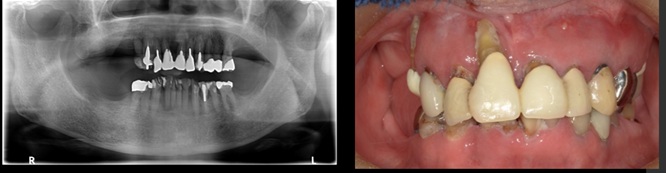

下顎管まで近いケースショートインプラントと垂直GBR(骨造成)で対応した →インプラント埋入

治療前

治療後

施術名 | インプラント埋入垂直GBR(骨造成) |

主訴 | 噛めない |

施術の副作用(リスク) | 感染脱落 |

施術の価格 | 1本GBR5万~10万(税抜き)+インプラント埋入補綴まで35万(税抜き) FGG5万 |

コメント | 下顎管まで近いケースショートインプラントと垂直GBR(骨造成)を同時に行いました |